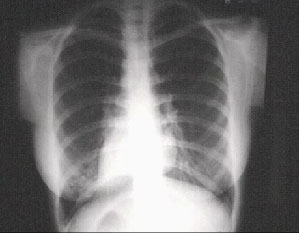

You are incorrect - our patient's chest X rays are entirely normal.

Your choice: Dextrocardia

This chest X ray demonstrates dextrocardia, with the cardiac apex on the right. Note that the stomach bubble is also on the right, thus demonstrating situs inversus. While dextrocardia may be found in patients who are otherwise normal, when it occurs in the absence of situs inversus, a very high incidence of congenital heart disease is found.